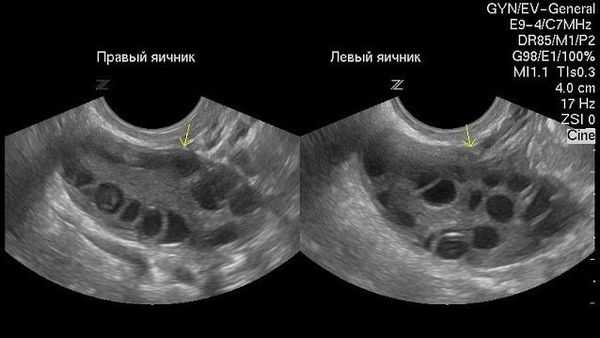

Название этого заболевания происходит от морфологических изменений в яичнике - в них образуется большое количество мелких кист, представляющих собой фолликулы, которые наполнены жидкостью и содержат незрелые яйцеклетки. Кисты располагаются по внешнему краю каждого яичника. Заболевание представляет собой патологию структуры и функции яичников на фоне нейрообменных нарушений с хронической ановуляцией и гиперандрогенией [5]. Оно является частой причиной нарушения менструальной и репродуктивной функции у женщин (у подавляющего большинства женщин с данным заболеванием диагностируется первичное бесплодие).

Как выглядят при ультразвуковом обследовании нормальные яичники:

Как выглядят яичники при наличии кист: